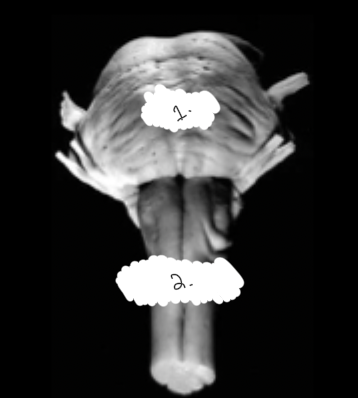

label this diagram

1: pons

2: medulla